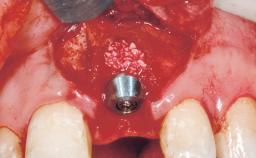

Immediate Placement of an Implant in a Maxillary Right Central Incisor Site

A 30-year-old female patient was referred to the office for the treatment of tooth 11. Her chief concern at the initial visit was to inquire, “Why is my tooth pink?” Upon clinical examination, it was determined that tooth 11 had a previous history of trauma and that the clinical crown had become noticeably pink in color as a result of internal resorption. This diagnosis was confirmed radiographically, indicating a large radiolucency involving the central and distal portions of the clinical crown. It was determined that restoration of this tooth was not possible, and that extraction was indicated. The presence of a mid-line diastema, which the patient wanted to reproduce, directed the treatment plan for tooth replacement utilizing a dental implant.

Bone Augmentation Horizontal|Simultaneous

Augmentation Materials Autogenous chips|Membrane

Placement Protocol Immediate implant placement

Tooth Site Maxillary incisor or canine

Socket Morphology Single-root socket

Socket Integrity Sufficient, with intact bone walls

Bone Volume Sufficient, with intact walls